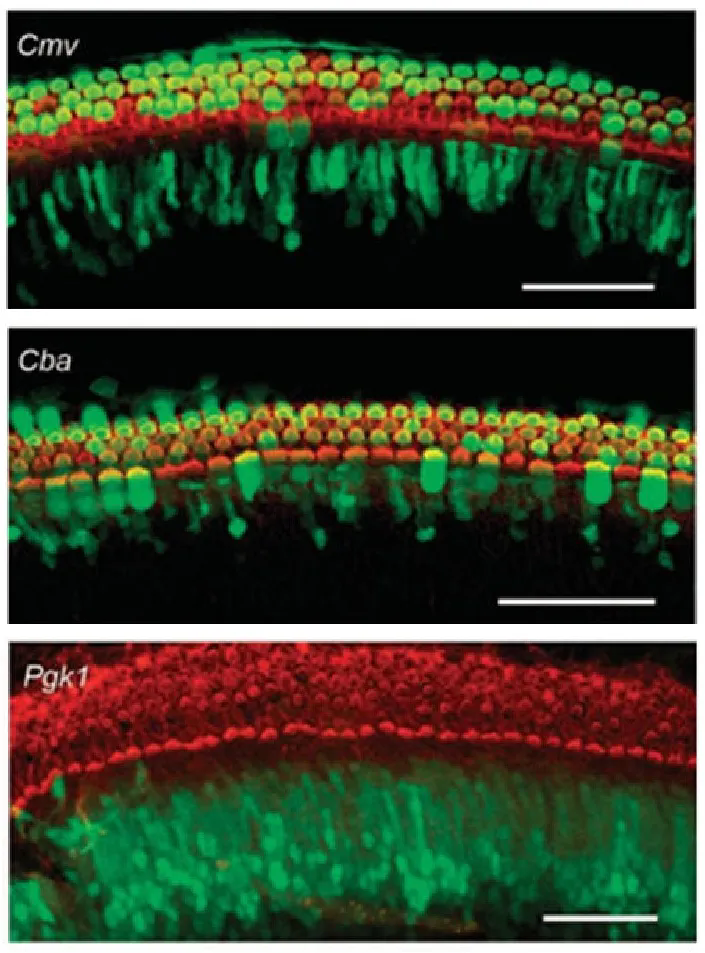

· 組成型啟動子

CMV和CBA已(yi)被證明可驅(qu)動(dong)耳蝸毛細(xi)胞(bao)(bao)、支(zhi)持細(xi)胞(bao)(bao)等(deng)多種細(xi)胞(bao)(bao)類型中的(de)轉基因表達(da)(da)����,Pgk1(磷酸(suan)甘油(you)酸(suan)激酶1)啟動(dong)子(zi)則可驅����(qu)動(dong)外源基因在支(zhi)持細(xi)胞(bao)(bao)中表達(da)(da)。

圖2. CMV、CBA和Pgk1啟動子驅動外(wai)源基(ji)因在離體培養小鼠耳蝸細胞中的表達

(Askew C, et al.Sci Transl Med.2015)